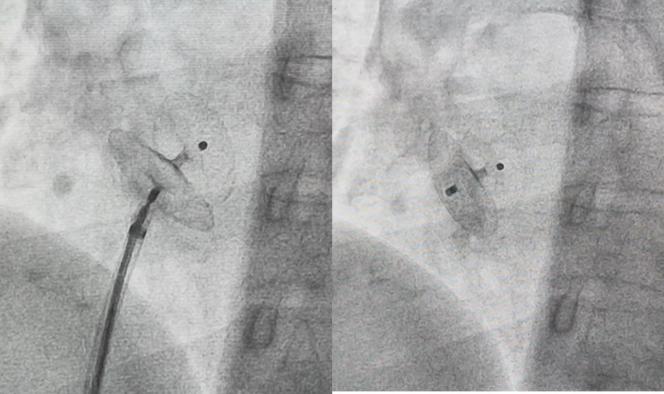

金山医院卵圆孔未闭多学科门诊组织心内科、神经内科、麻醉科、影像科专家讨论陈女士的复杂情况,最终制定阶段性治疗方法:心血管科团队通过微创介入手术成功实施卵圆孔未闭合封堵术,术中再次造影确定异常分流消失,一个封堵器同时封闭两个孔;第二天,麻醉科吴城孝医生在术后协助“神经阻滞止痛治疗”。通过“鸡尾酒”复合止痛方案阻断疼痛传导链,帮助患者缓解长期疼痛。